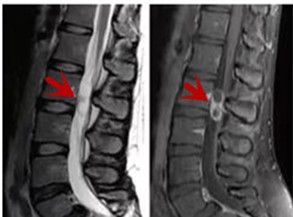

箭頭提示腰椎管內(nèi)腫瘤

紅色箭頭提示新鮮骨折,黃色箭頭提示陳舊性骨折